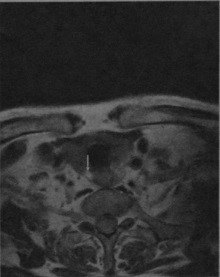

Аденома паращитовидной железы, расположенная справа и сзади от щитовидной железы. МРТ, Т2-взвешенное изображение без контрастирования: опухоль выглядит как округлое образование с высокой интенсивностью сигнала (стрелка).